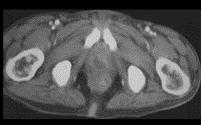

问题 男,35岁,右侧腰部疼痛伴发热,请根据所示图像,选择最可能诊断 ( )

选项 A.右侧肾脓肿 B.右侧单纯性肾囊肿 C.右侧囊性肾癌 D.右肾转移瘤 E.前列腺脓肿

答案 AE